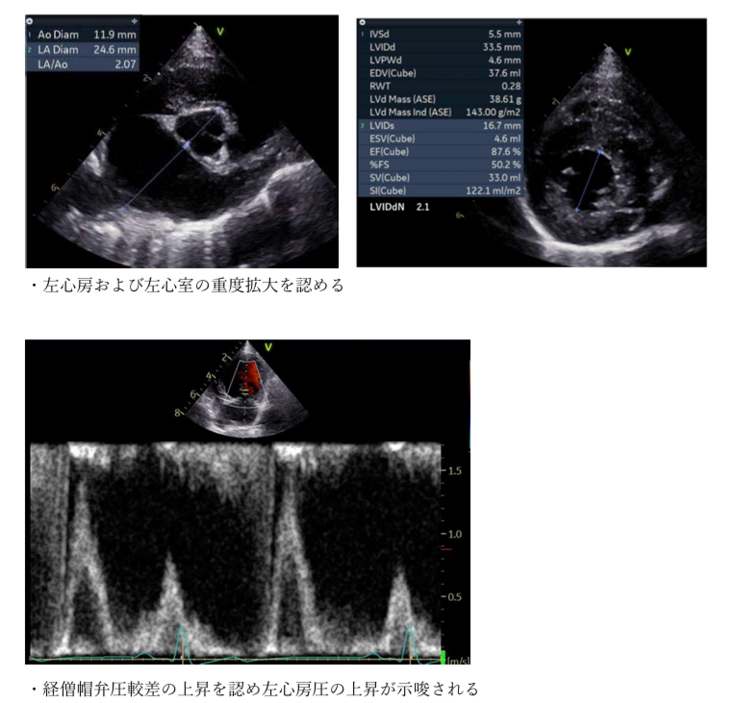

※エコー画像・診断データ・通院記録は信頼性のためページ下資料欄に掲載しております。

【資料欄】(個人情報保護のため、一部モザイク処理させていただいております)

・病院から頂いた所見データ(2025.4.16)